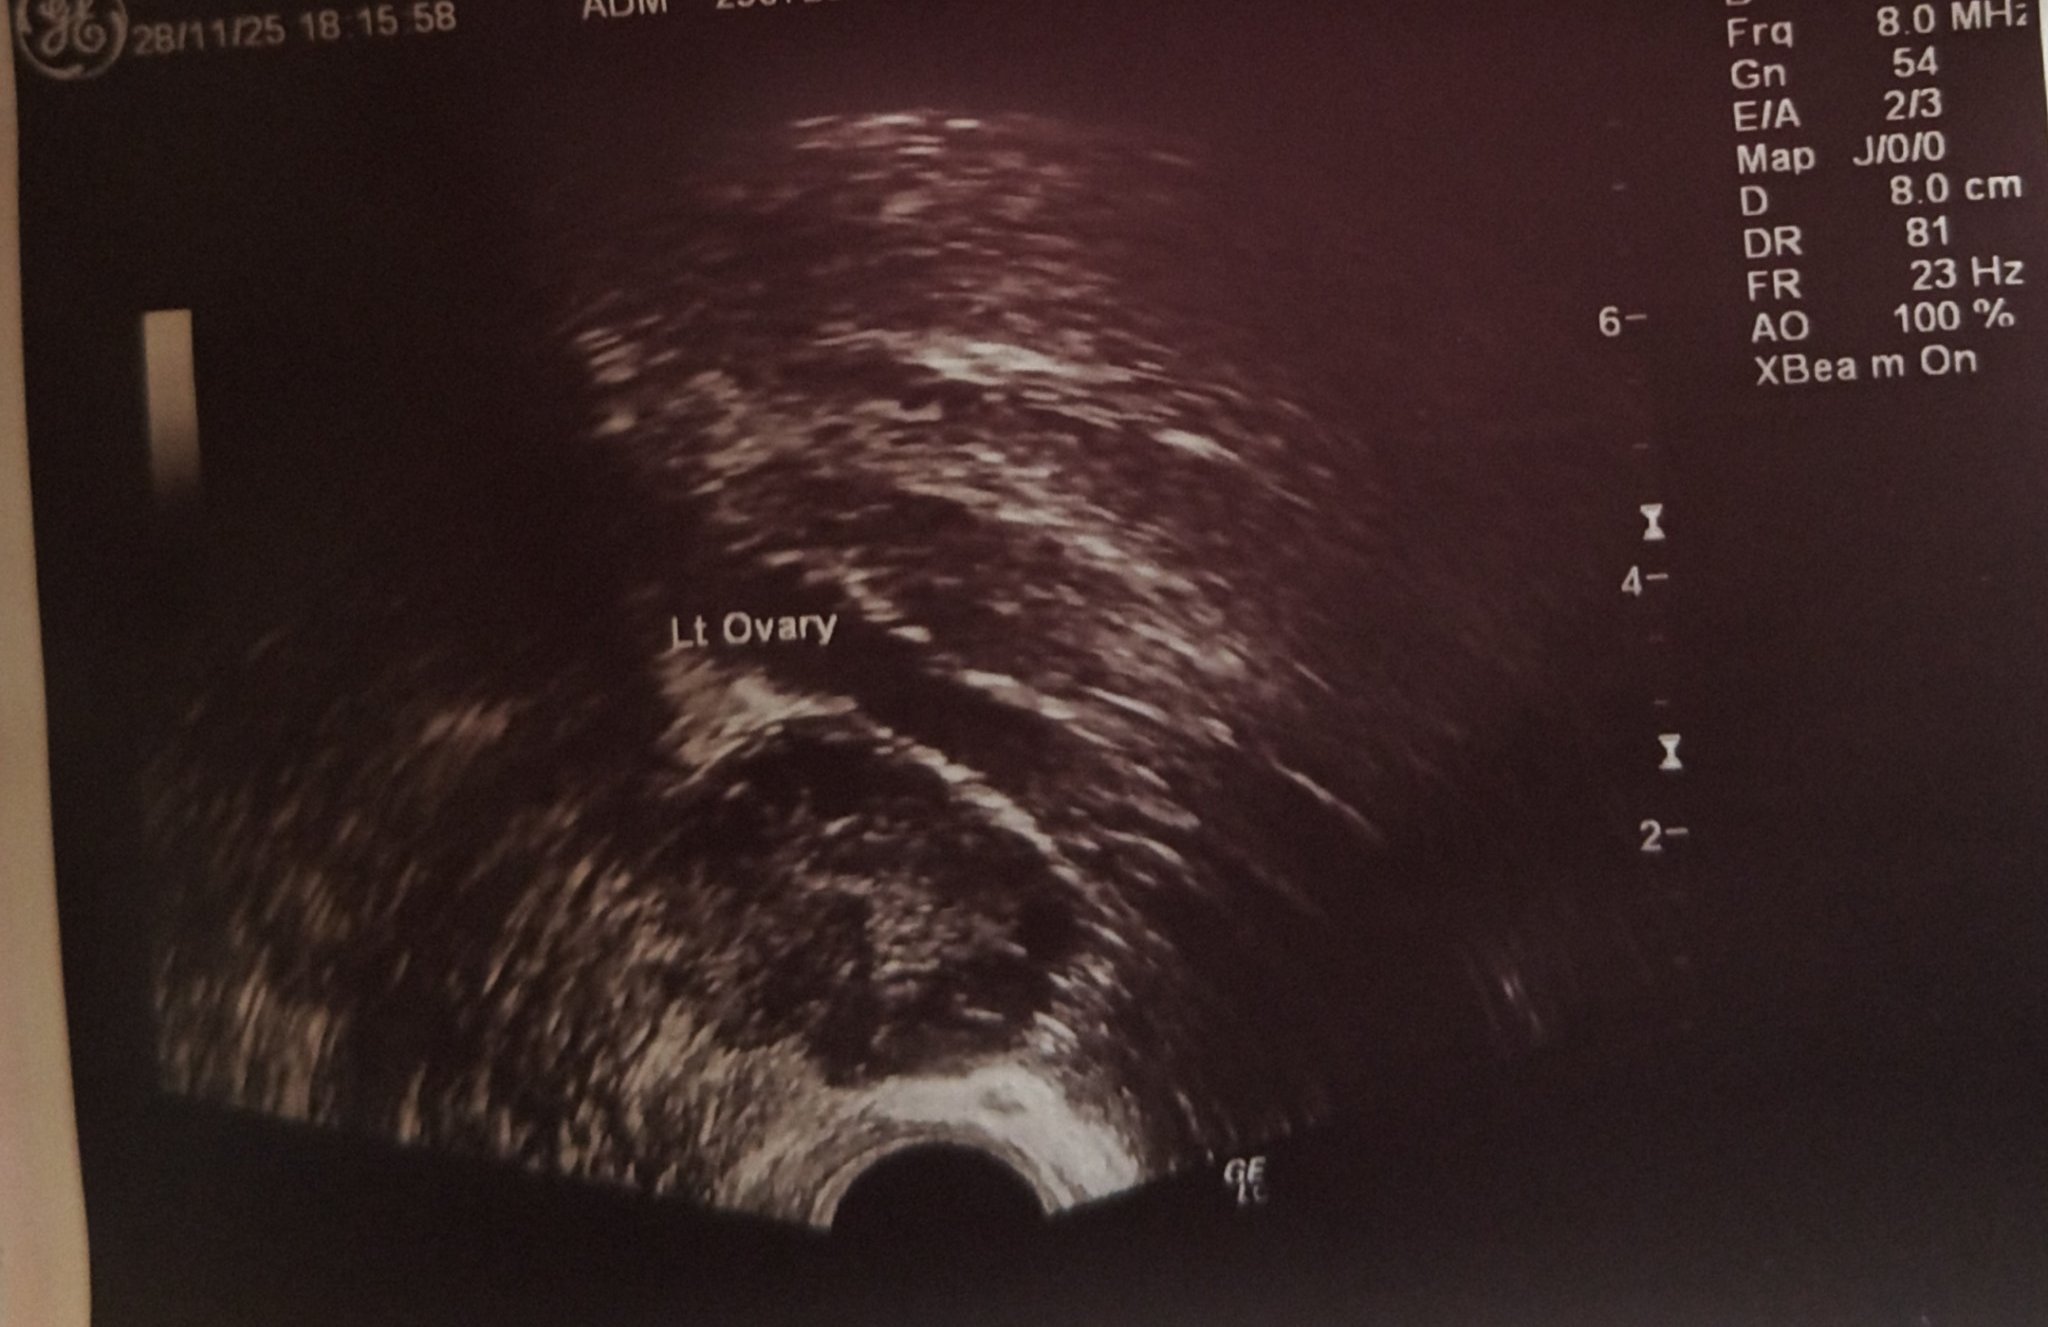

Какво представлява жълтото тяло на ехографската снимка?

Какво представляват черните точки в матката на ехографската снимка?